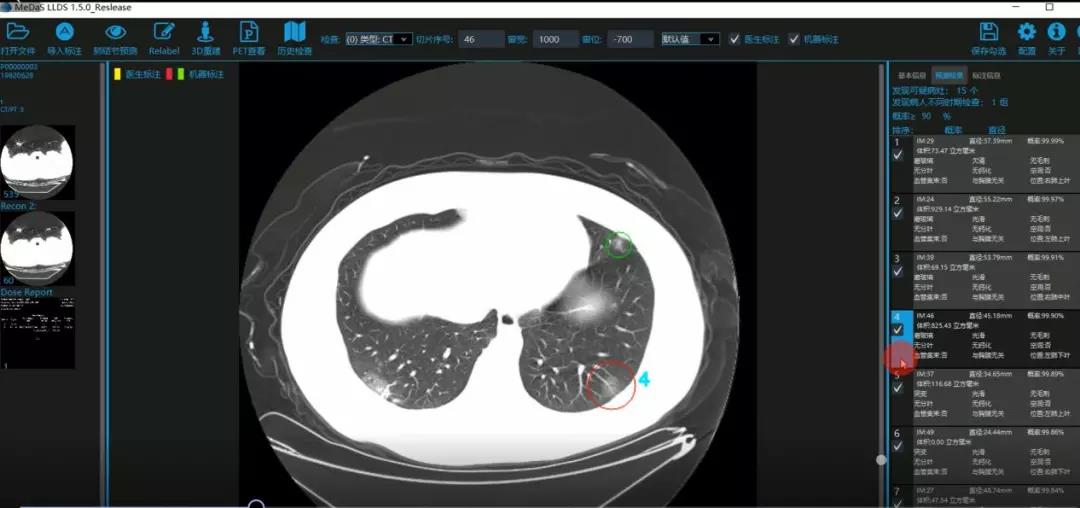

西电BB贝博艾弗森智能软件与系统新技术研究所副教授张亮的爱人是西安交通大学第二附属医院抗疫一线的影像科医生,疫情发生以来,他们讨论最多的就是新型冠状病毒感染者的早期诊断问题。作为一名医护家属,身为高校科研工作者,张亮深知快速准确地诊断新冠肺炎早期患者对控制和防治疫情的重要性和挑战性。他与团队成员主动出击,通过远程网络会议,在前期医学影像处理的研究基础上加速科研攻关,反复讨论方案,屡次设计模型,与上海宽带技术及应用工程研究中心、上海交通大学医公司附属瑞金医院等合作单位的人员多次标注整理患者肺部CT影像数据到深夜。与此同时,他们依托上海瑞金医院、西安交通大学第二附属医院等的新冠肺炎疑似、确诊患者肺部CT影像,通过综合分析新冠肺炎患者的肺部CT影像特点(磨玻璃、体积大小、位置等特征),张亮团队加快技术攻关,设计开发了基于深度学习的新型冠状病毒的早期检测筛查模型系统。

对应新冠肺炎CT病灶检测效果

令人欣喜的是,通过对实际门诊数据排查测试,该模型可以减轻医护人员近80%的工作量,新冠肺炎患者的检测召回率超过95%。目前,模型系统正在进行最后的调试工作,很快投入到“战疫”一线,缓解医护人员紧缺、确诊检测工作耗时较长等问题,减少医护人员的工作时间和劳动强度,提高工作效率。